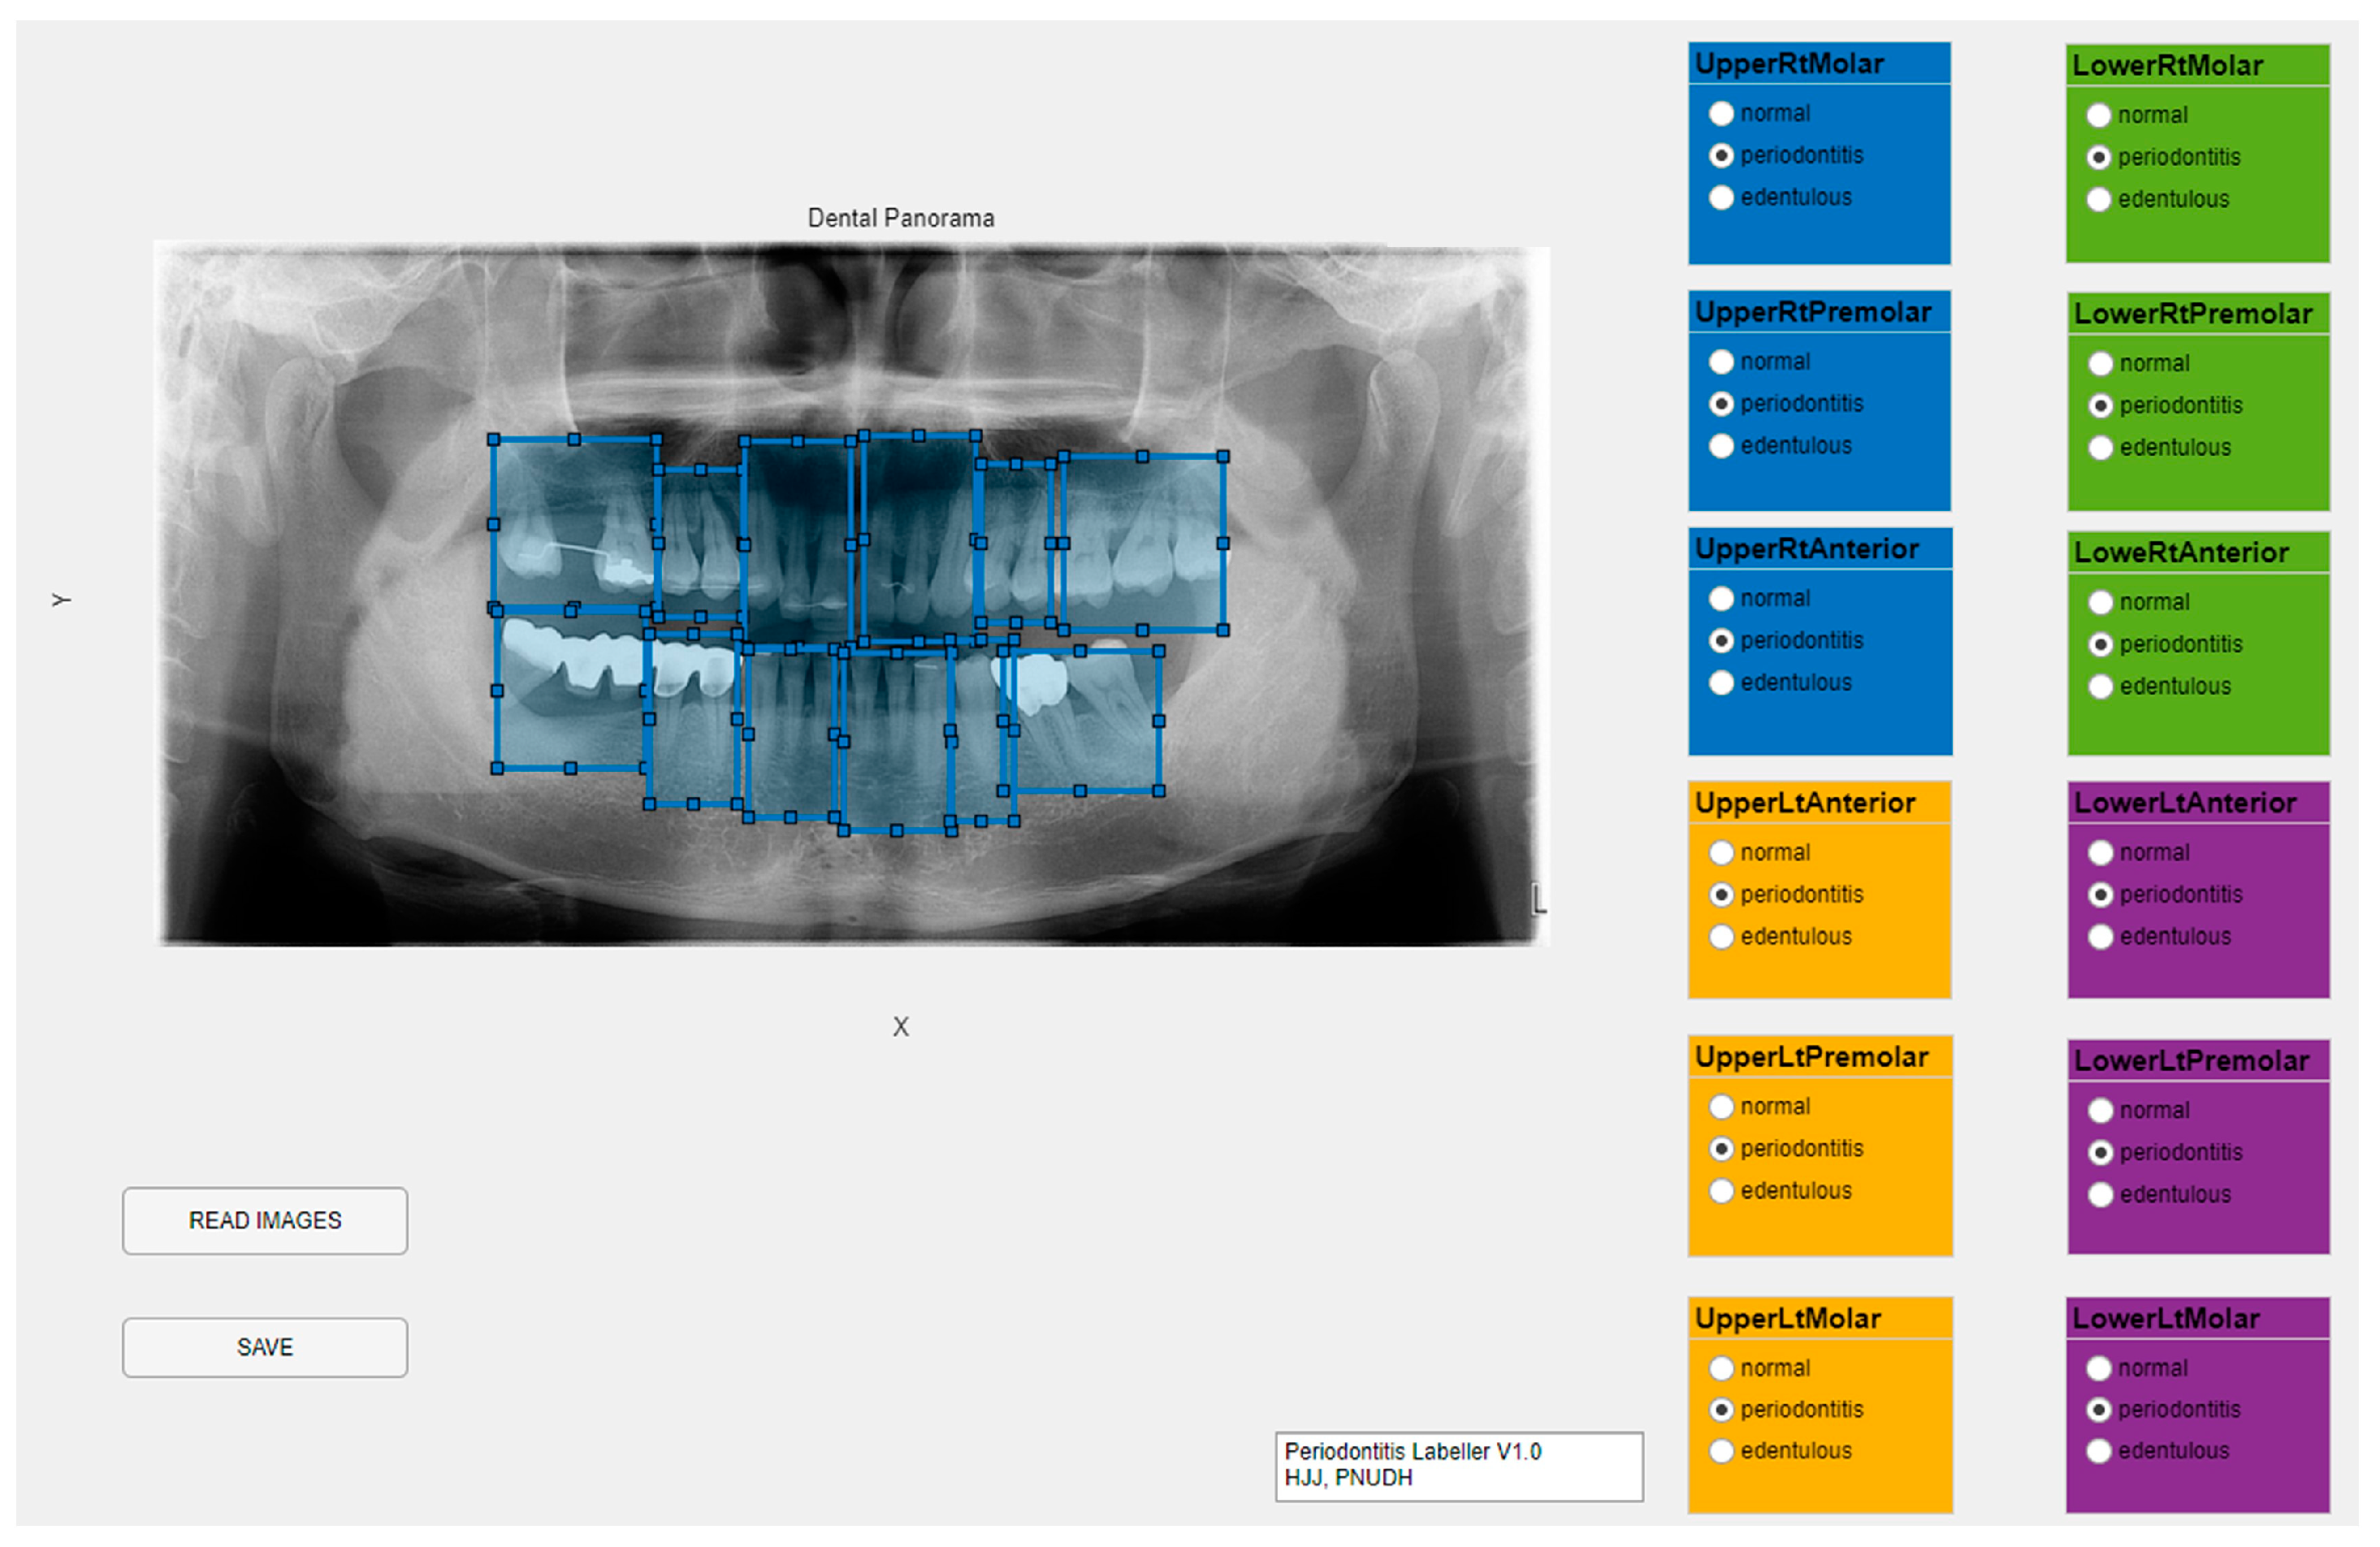

2. Materials and Methods

2.2. Data Set

2.3. Experiment